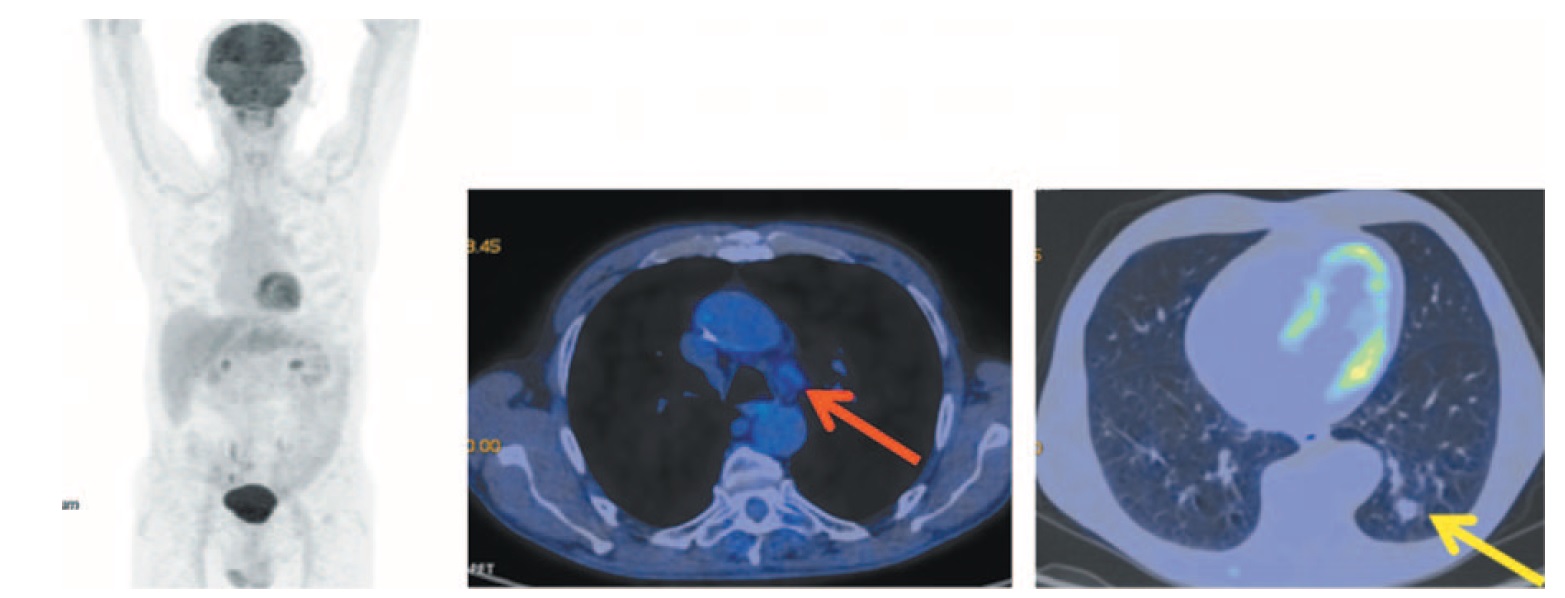

После 6-го введения атезолизумаба выполнена ПЭТ/КТ с 18F-ФДГ. Выраженная положительная динамика за счет сокращения размеров опухоли в нижней доле левого легкого до 15×16×15 мм (ранее 41×57×81 мм) без метаболической активности 18F-ФДГ. Восстановление объема легочной ткани левого легкого. В S10 на месте ателектаза сформировался пневмофиброз в виде узлового образования размером до 15×16 мм, без метаболической активности 18F-ФДГ. Отмечается уменьшение размеров паратрахеальных, бифуркационных лимфоузлов, включая аортопульмональное окно без фиксации радиофармпрепарата (РФП). В головном мозге в режиме рентгеновской КТ очаговых образований не выявлено (рис. 2).

Рис. 2. Больной П., 76 лет, после 6 введений атезолизумаба (через 3 мес от начала лечения). На МIP- и аксиальных ПЭТ/КТ-проекциях отмечается регрессия надключичного лимфоузла справа. Вентиляция легочной ткани левого легкого восстановлена. В S10 на месте ателектаза сформировался пневмофиброз с включением узлового образования в структуру размером до 15×16×15 мм (ранее размером до 41×57×81 мм) с четким контуром без метаболической активности ФДГ (желтая стрелка). В плевральных полостях и полости перикарда экссудата нет. Размеры паратрахеальных, бифуркационных узлов и аортопульмонального окна уменьшились без фиксации РФП (красная стрелка). / Fig. 2. A 76-year-old patient P. after 6 injections of atezolizumab (3 months after the start of treatment). MIP and axial PET/CT images show the regression of the right supraclavicular lymph node. Right lung ventilation is restored. In S10 the pneumofibrosis at the site of atelectasis with a nodular formation in a structure measuring 15×16×15 mm (previously measuring 41×57×81 mm) with the clear margins without FDG metabolic activity (yellow arrow) is detected. There is no exudate in the pleural and pericardial cavities. The size of paratracheal, bifurcation and aortopulmonary window lymph nodes decreased and without uptake of the RFP (red arrow).